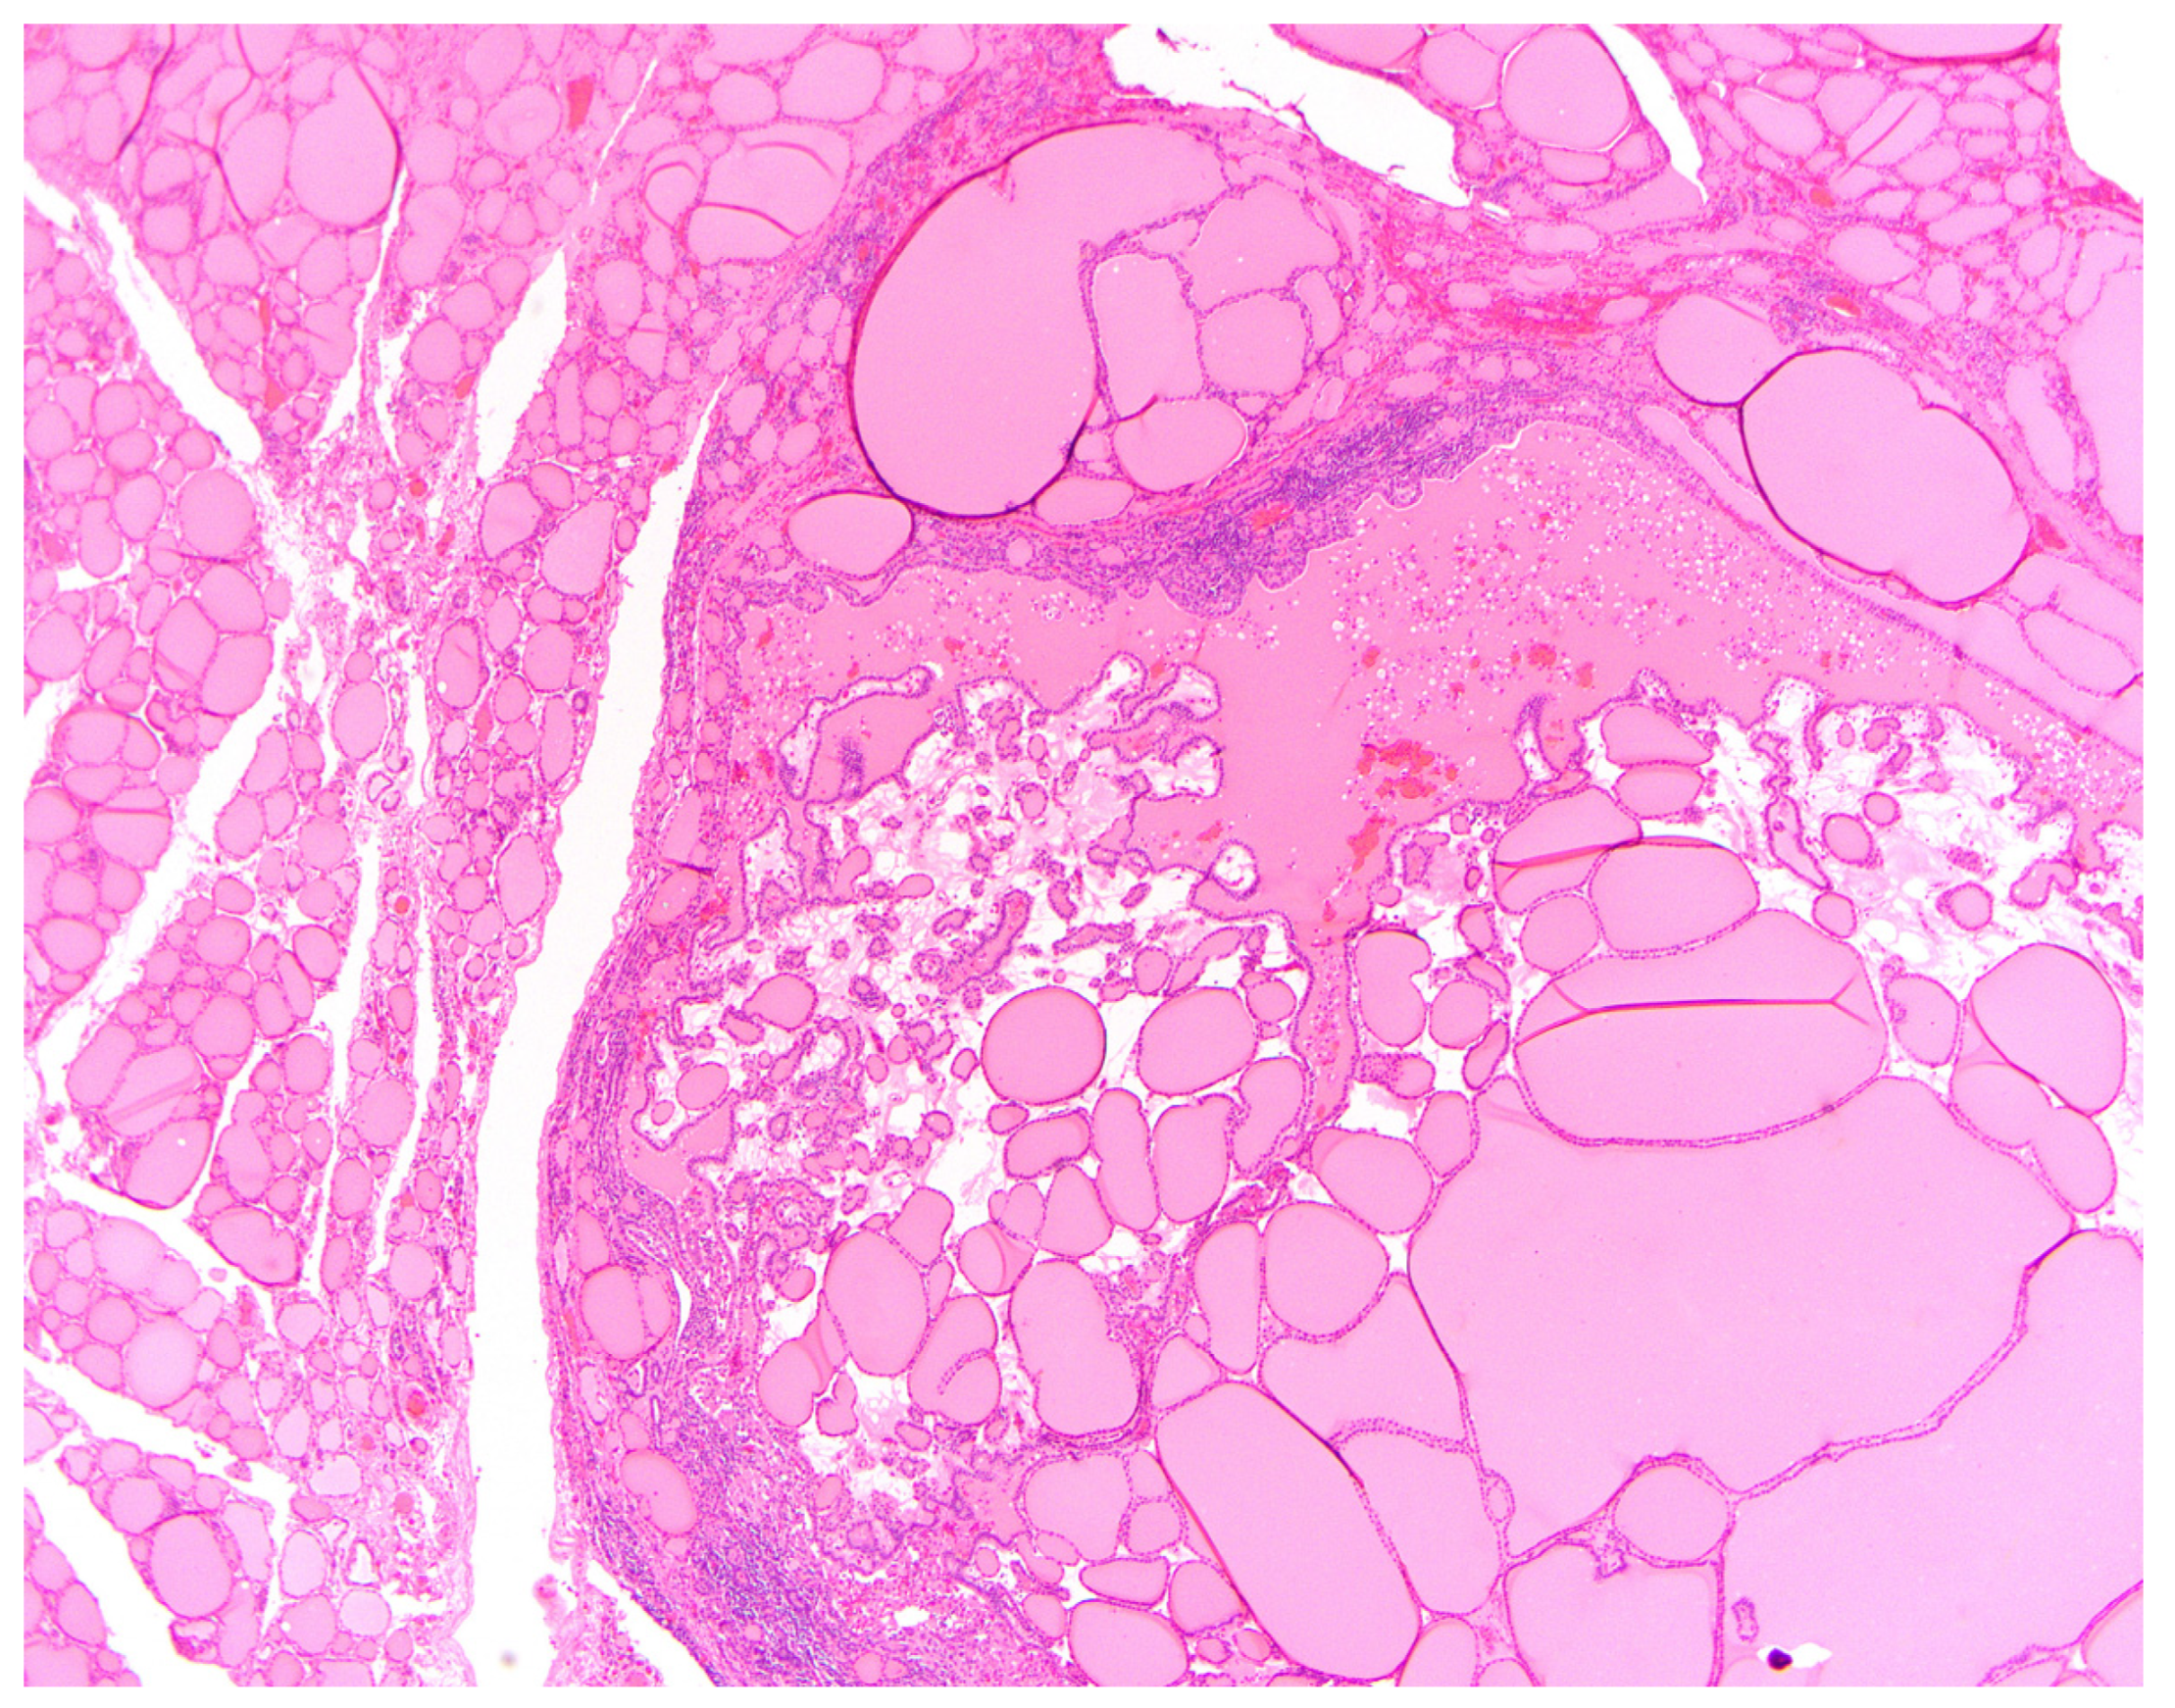

5.1. Thyroid Follicular Nodular Disease/Multinodular Goiter